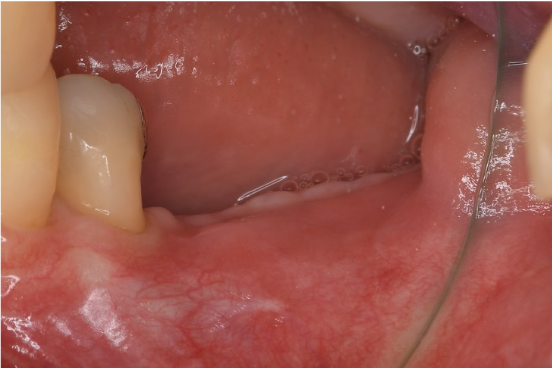

症例3

| 項目 | 詳細 |

|---|---|

| 患者様データ | 50代 男性 |

| 来院時の主訴 | 「左下で噛むと違和感がある。」 |

| 医院の診断 | 左下第二大臼歯の歯根破折 |

| 通院期間 | 9か月 |

| 来院回数 | 12回 |

| 治療費 | 総額:835,000円(税抜) 【内訳】 インプラント埋入手術250,000円、GBR(骨再生手術)150,000円、2次手術+FGG(遊離歯肉移植術)55,000+60,000円、仮歯30,000円、インプラント上部構造(セラミッククラウン)170,000円、隣在歯セラミッククラウンのやりかえ120,000円 |

| リスクと副作用 | 定期的なメンテナンスが必要、術後若干の腫れと痛み |

| ここがこだわりのポイント!☝ | インプラント周囲に角化歯肉と言われる健常な歯肉がなかったので、口蓋からの歯肉移植を行っています💡この角化歯肉がないと、インプラントをしてもうまく歯磨きができないことがあります。 |